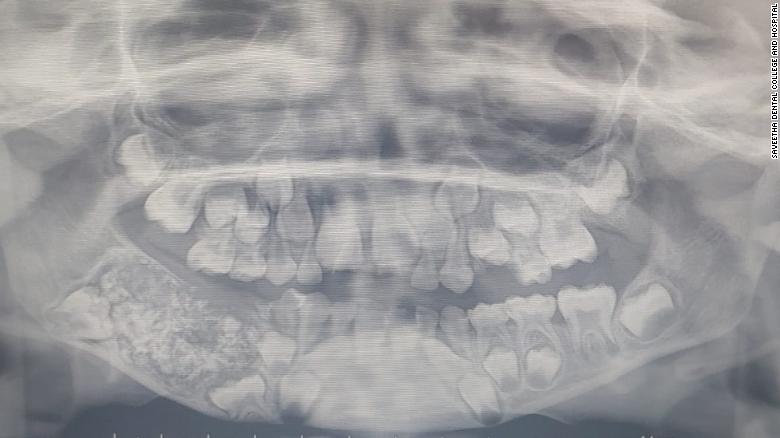

Рентген челюсти 7-летнего ребенка. Фото: Saveetha Dental College and Hospital

Мальчик был госпитализирован в южном городе Ченнаи из-за отека и болей в нижней челюсти. На рентгене врачи увидели в нижней челюсти мальчика мешок, заполненный недоразвитыми зубами.

"Всего было 526 зубов, размер которых варьировался в диапазоне от 0,1 мм до 15 мм. Даже у самых маленьких зубов имелся корень и эмаль", – заявила доктор Пратиба Рамани, руководившая операцией.